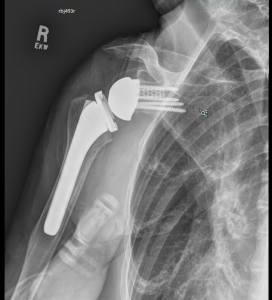

CASE 1

This is a 74-year-old male with history of prior failed cuff repair now with rotator cuff tear arthropathy. There is significant posterior wear of 18 degrees combined with 10 degrees of superior inclination. This is a common wear pattern in rotator cuff tear arthropathy. By planning the posterior superior augment preoperatively, I was able to move the center starting point slightly posterior and place it in 6 degrees of retroversion, allowing the cage to stay within the vault and ream almost no bone. The 10-degree superior portion of the augment fit almost perfectly. Without the preoperative planning and the GPS navigation it would have been easy to ream away significant bone anteriorly to attempt a correction of the version. There also would have been no way to determine how much retroversion I was leaving the implant in order to ream minimally.